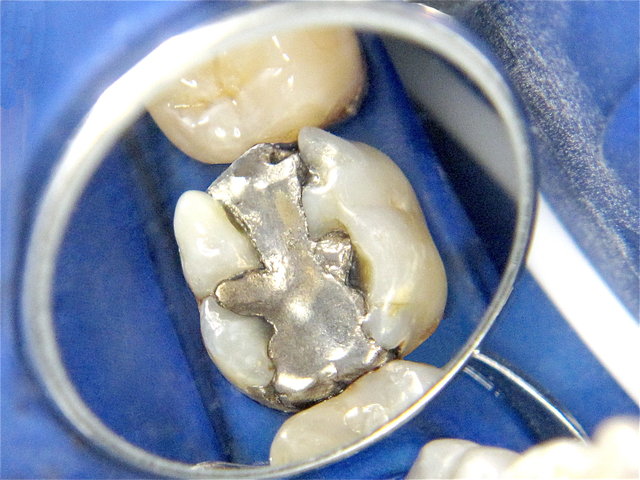

Alte undichte Amalgam-Füllungen mit Karies und Rissen ...

Composit-Füllungen by CLINICDENT ✓